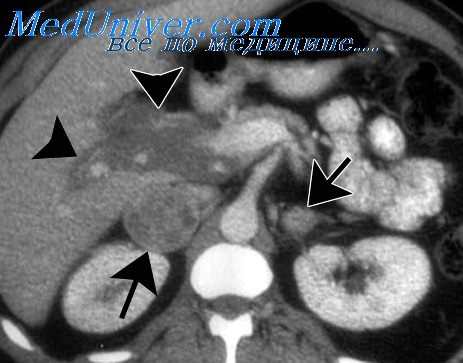

В этих случаях диагноз феохромоцитомы может быть поставлен только на основании повышения выделения катехоламинов с мочой, а локализация опухолевого процесса устанавливается путем тщательного и детального рентгенологического исследования (пневморен, оксисупраренография, пиелография и др.).

Резко участились приступы болей в животе, которые сопровождались еще большим повышением артериального давления, усилением тремора и потливости. Основной обмен оказался резко повышенным (+66%) при нормальных цифрах поглощения J131, гипергликемичсская сахарная кривая. Содержание адреналина в крови было значительно выше нормы — 4у%. Был поставлен диагноз феохромоцитомы с выраженной адреналиновой интоксикацией, стойкой гипертонией. При оксисупраренографии были обнаружены изменения со стороны левого надпочечника, и больная была переведена в хирургическое отделение для удаления опухоли. На операции обнаружена феохромоцитома левого надпочечника, подтвержденная гистологически.